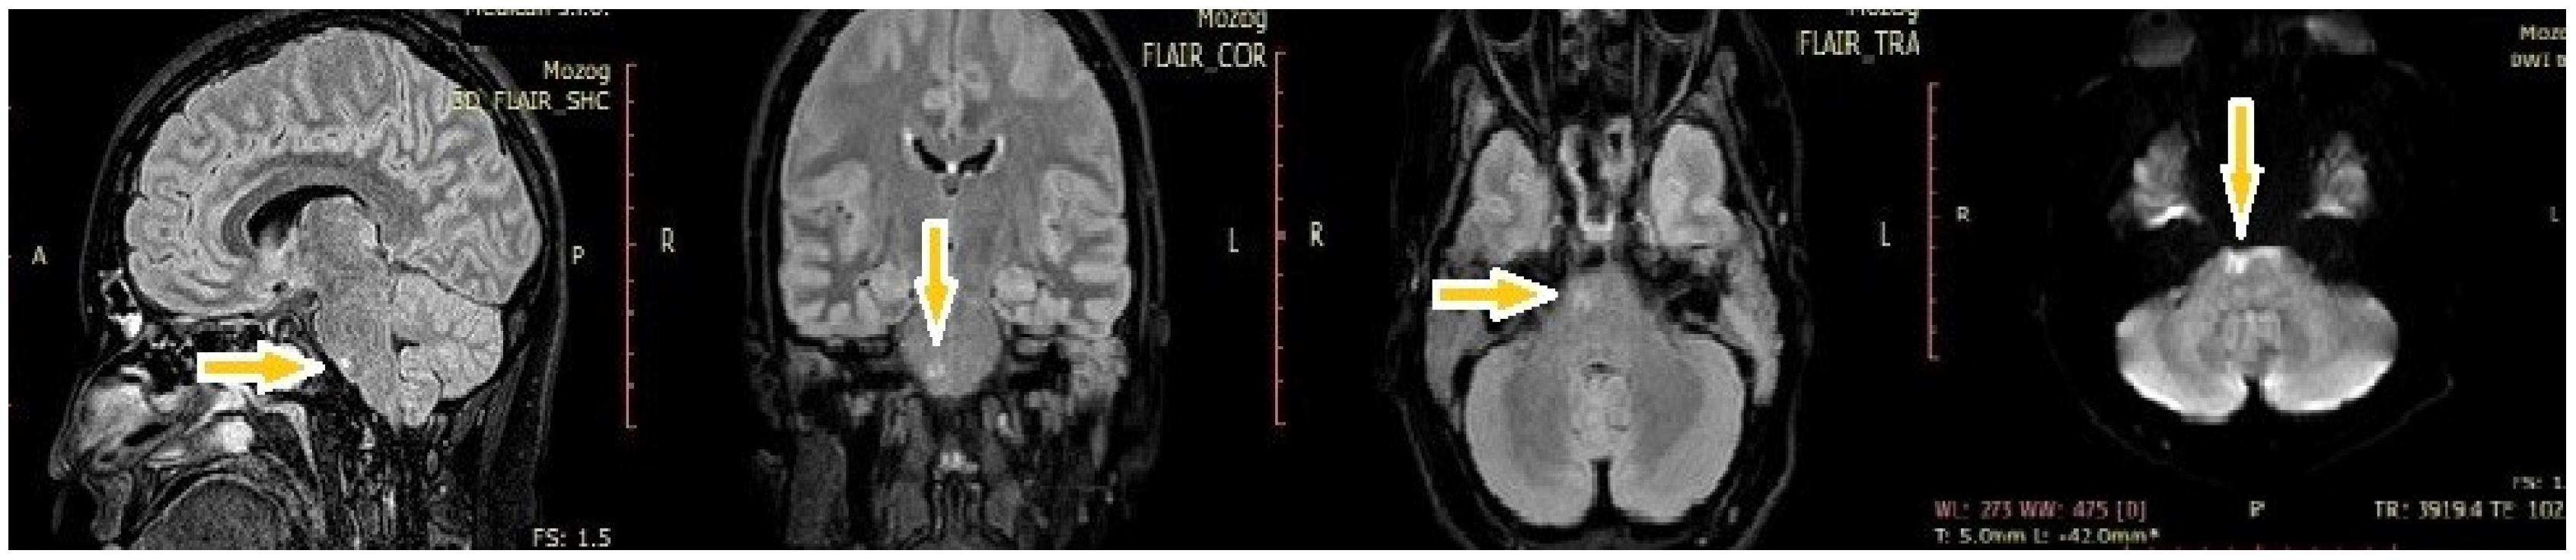

After six days, the patient became increasingly somnolent and verbally unresponsive. A physical neurological examination revealed somnolence, orofacial dyskinesia, and spastic tetraplegia with generalized tonic–clonic seizure. She was transferred to the neurological intensive care unit (ICU) and underwent other examinations. Control brain MRI showed an abnormal focal brainstem lesion. FLAIR- and T2-weighted MRI showed that the lesion was pontine hyperintense and non-enhancing after the administration of gadolinium chelating agents. It also did not display restricted diffusion (Figure 1).

Figure 1. MRI findings of hyperintensities in the brainstem (yellow arrows) in FLAIR-weighted images and DWI.